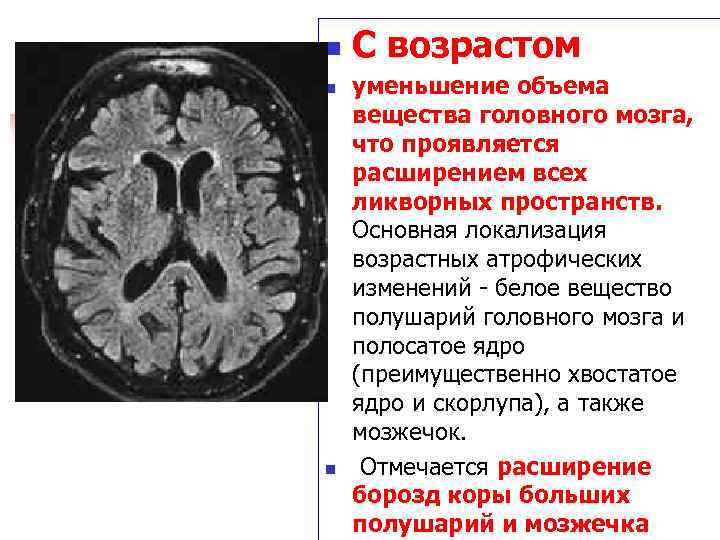

Признаки умеренно выраженной наружная

Признаки умеренно выраженной наружная 113 фото